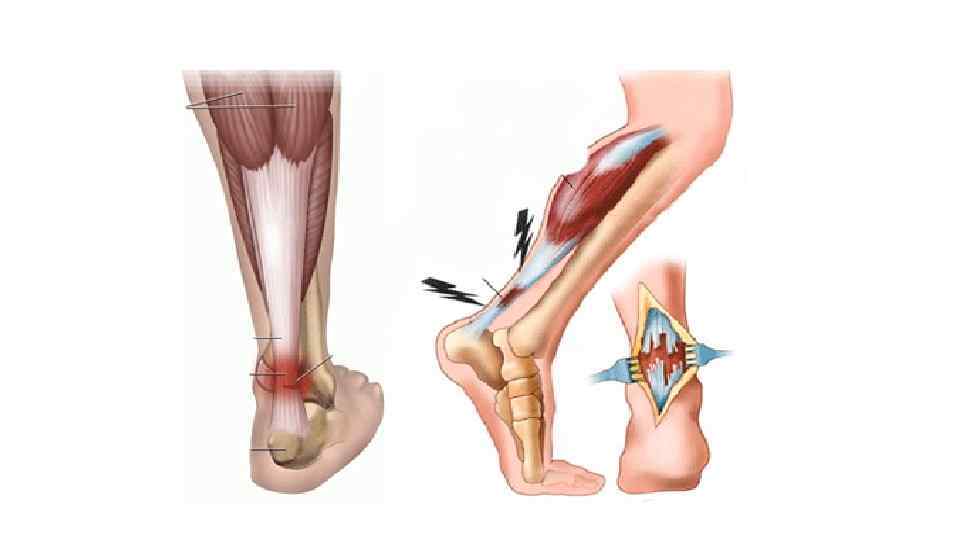

3) Разрыв • Нарушение анатомической целостности тканей, вызванное силой, превышающей их эластические возможности. • К: боль, отек, старается беречь место травмы. • О: обширное кровоизлияние, патологическое увеличение объема движений в суставе, резкое нарушение функции конечности. • Если разрыв мышцы, то можно увидеть брюшко мыш. культи (при сокращении) • Д: Rg для искл. перелома

• ПП: холод, тугая повязка, обезболить. • Л: гипсовая иммобилизация на 4 -6 недель, максимально отклонив в сторону повреждения, возвышенное положение, УВЧ. После снятие гипса: ЛФК, массаж, теплые ванны, электрофонофорез прокаина и поливитаминов. Х. Л: сшивание связок, пластика.

Разрыв мышц (Скот Мендельсон)